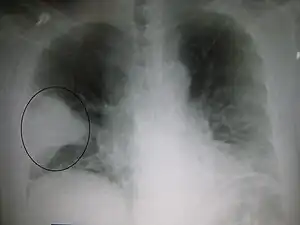

A chest X-ray showing a very prominent wedge-shape area of airspace consolidation in the right lung characteristic of acute bacterial lobar pneumonia.